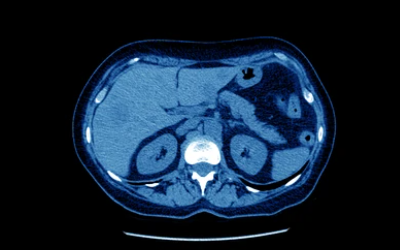

간암은 어떻게 진단하나요?

간암은 일반적으로 혈액검사, 초음파, CT, MRI, PET 등의 검사를 통해 진단합니다. 간암의 종류와 진행 정도에 따라 검사 방법이 달라질 수 있습니다.